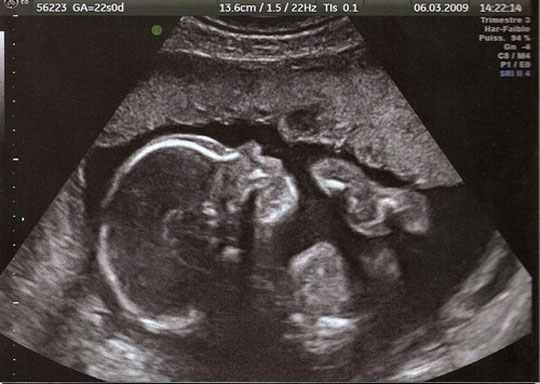

Les grandes avancées de la médecine

Ce diaporama permet de retracer une partie de l’histoire de la médecine à travers ses grandes avancées techniques ou ses découvertes. De l’invention du stéthoscope à l’arrivée de l’IRM, une vingtaine d’images accompagnées d’informations viendront en support pour alimenter une discussion autour de la vision de chacun sur ces progrès médicaux qui ont changé notre quotidien. N'oubliez pas de "dezipper" le diaporama avant de le lancer.

'name' => 'Echographie...'